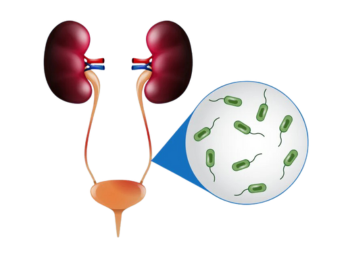

Urinary Tract Infections

02. Stone removal and urinary tract management.

Effective treatment for kidney and urinary stones along with complete care for infections, obstructions, and bladder disorders.